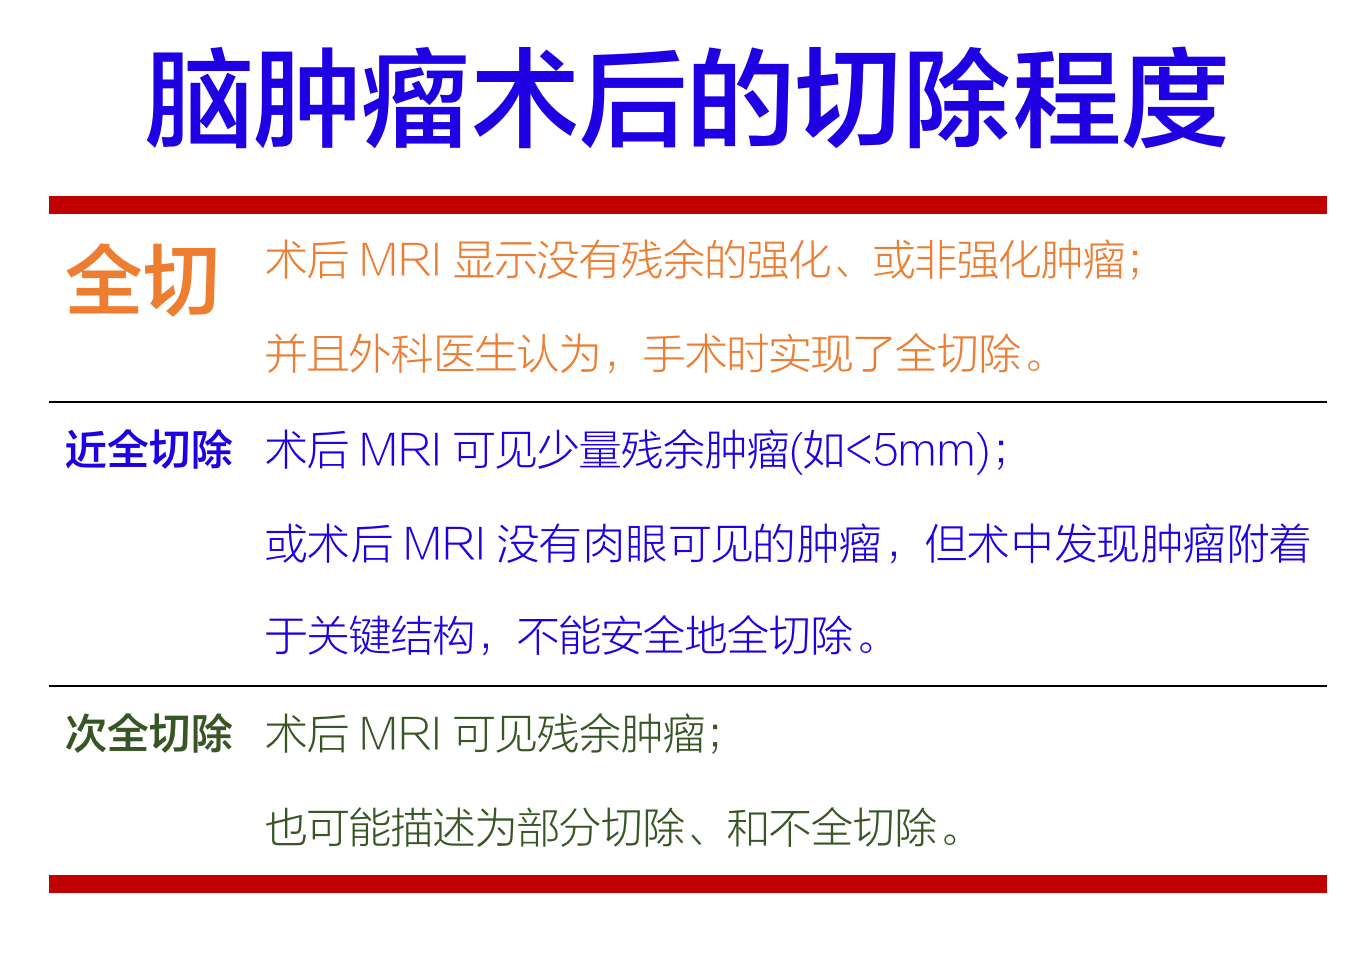

尽管切除程度的相关术语会有差异,但通常定义如下:

任何级别的室管膜瘤,在全切除后都应直接接受适形放疗,除非患者参加经审批的前瞻性临床试验或者年龄非常小(例如<1岁)。